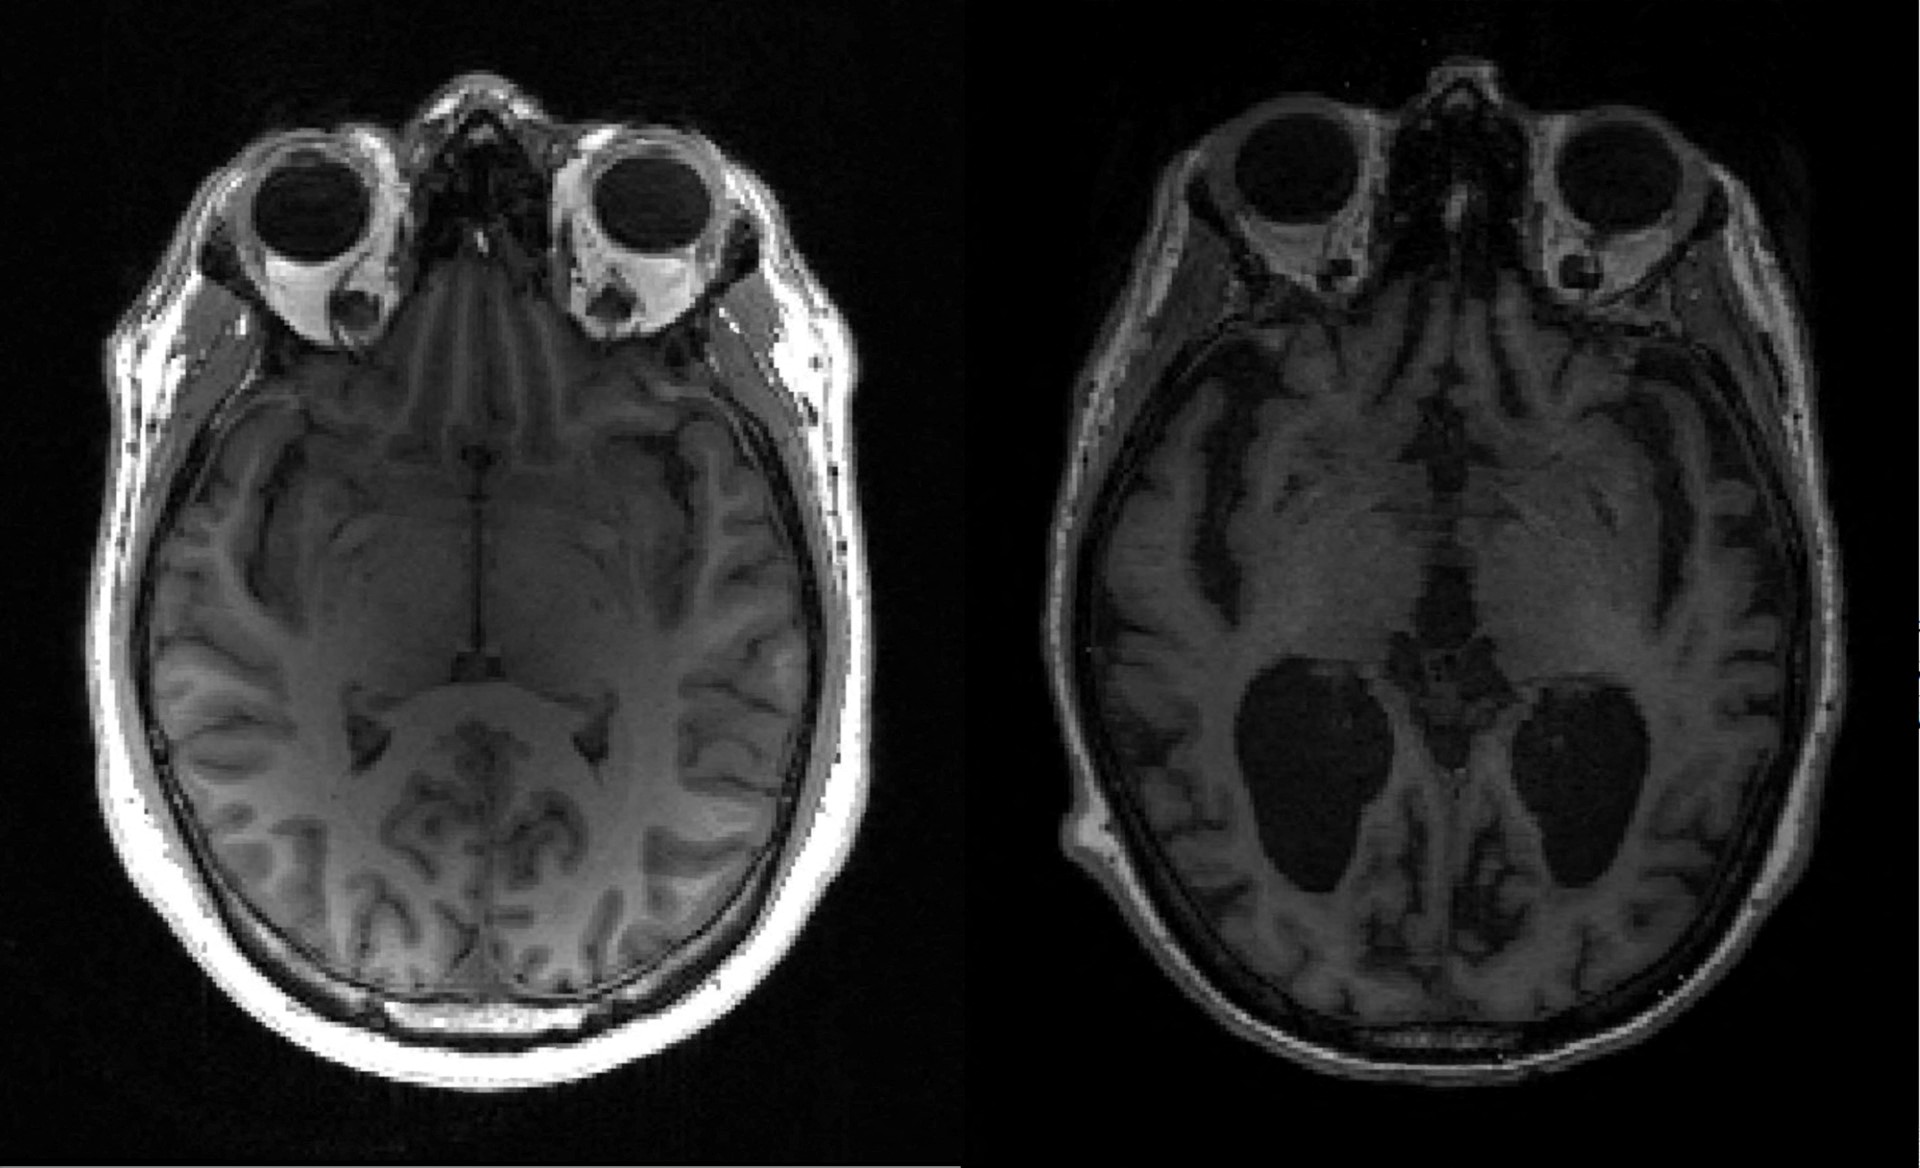

Μέχρι σήμερα, οι πιο αξιόπιστες μέθοδοι για την ανίχνευση της νόσου Αλτσχάιμερ απαιτούσαν επεμβατικές και δαπανηρές τεχνικές, όπως η λήψη εγκεφαλονωτιαίου υγρού. Οι επιστήμονες διερευνούν εδώ και χρόνια τη δυνατότητα εντοπισμού της νόσου, η οποία προσβάλλει 800.000 άτομα μόνο στην Ισπανία, με μια εξέταση αίματος, λόγω των δυνατοτήτων της να βελτιώσει την έγκαιρη διάγνωση.

Σύμφωνα με τον Ελόι Ροντρίγκεζ, επικεφαλής του Τμήματος Νευρολογίας στο Πανεπιστημιακό Νοσοκομείο Marqués de Valdecilla-IDIVAL, η πρόοδος αυτή “θα συμβάλει στον εκδημοκρατισμό της βιολογικής διάγνωσης ακριβείας της νόσου Αλτσχάιμερ”, η οποία θα αποφύγει σε πολλές περιπτώσεις πιο επεμβατικές ή δυσπρόσιτες τεχνικές, όπως η οσφυονωτιαία παρακέντηση ή η PET αμυλοειδούς, μια πολύ ακριβή απεικονιστική εξέταση. Ο εμπειρογνώμονας είναι αισιόδοξος για τη δυνατότητα επέκτασης της χρήσης αυτού του δείκτη “από εξειδικευμένες σε λιγότερο εξειδικευμένες επισκέψεις”.ω